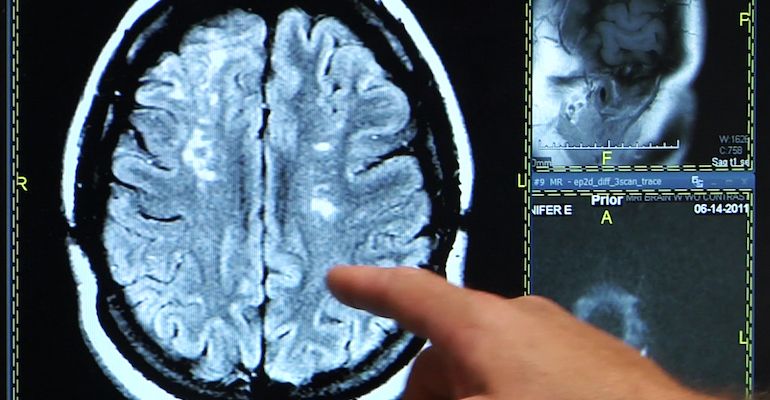

Potrivit proiectului de ordin publicat de Ministerul Sănătății, 41 de spitale vor face tromboliză intravenoasă pentru pacienții cu accident vascular cerebral (AVC) acut. Tromboliza este o perfuzie ce le este administrată pacienţilor care au suferit un accident vascular cerebral ischemic. Practic, substanţa dizolvă cheagul format pe vasul de sânge. Programul va fi extins la nivel național, dacă noul proiect trece nemodificat de faza dezbaterii publice.Patru persoane mor în fiecare zi din cauza unui accident vascular cerebral, motiv pentru care autoritățile au decis extinderea programului. Conform documentului citat, numai în cinci județe din România nu se va realiza intervenția. “Scopul includerii celor 31 de noi unități sanitare în AP-AVC este un demers ce își propune să operaționalizeze la nivel național AP-AVC. Vine în întâmpinarea unei probleme de o importanță definitorie pentru sănătatea publică din România. Anterior acestei modificări, AP-AVC se desfășura într-un număr de zece unității sanitare pe raza a 6 județe și a Municipiului București. În urma modificărilor aduse prin prezentul proiect de ordin, rețeaua de unități sanitare capabile să ofere tratament acut intervențional prin tromboliză intravenoasă pacienților cu accident vascular cerebral ischemic acut va fi extinsă în 41 de spitale. Se află pe raza a 36 de județe și a municipiului București”, se arată în referatul proiectului.Încă 31 de centre au fost propuse. Aici pacienţii vor putea beneficia de singura procedură medicală care le poate salva viața în caz de AVC,